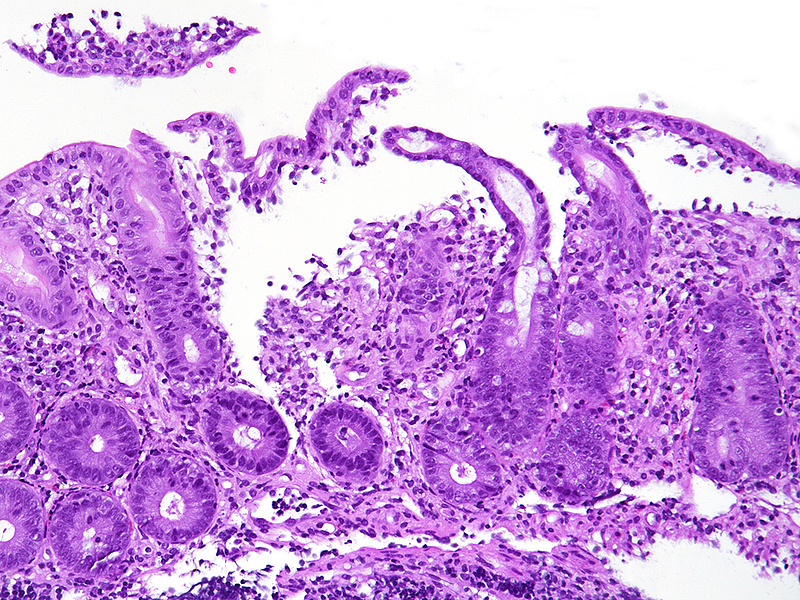

Biopsy material from the right colon in a 48-year-old male.

NSAID colonopathy.

Histologically, the architecture of the mucosa showed mild architectural distortion. The cell content within the mucosa was increased, with predominance of monuclear cells, that is, lymphocytes and plasma cells (Panels A-B). High magnification revealed mild basal plasmactytosis and additional neutrophil granulocytes in stroma and crypt epithelium (cryptitis) as well as clusters of eosinophils (Panel C). The crypt epithelium showed reactive changes, with loss of goblet cells, variation in nuclear size with small nucleoli, and increased apoptosis. Withered crypts were only occasionally seen (Panel D). Superficial erosion and regenerative epithelium were identified in the coecum (Panel E), with rare superficial intracapillary fibrin thrombi (Panel F).